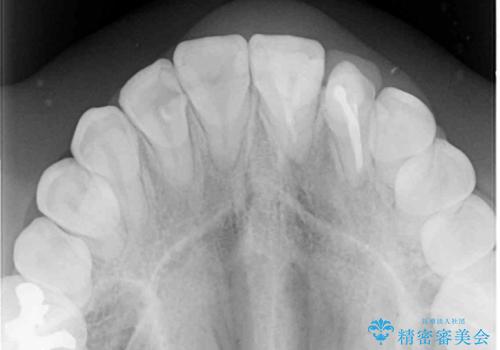

- 上下のデコボコと奥歯の咬みにくさを気にして来院された患者様です。

上顎骨の幅が下顎骨よりも小さいので、拡大装置により骨幅を広げて上下関係を改善し、その後インビザラインにて歯並びを整えることとしました。

上下の骨幅を改善したことで、スムーズに歯列矯正を行うことができました。

奥歯の咬み合わせを改善する必要があったため、治療は長期化しましたが、きっちりと仕上げることができました。